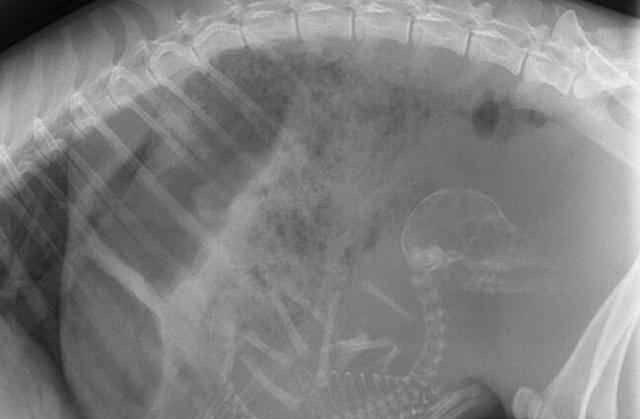

3.鲨鱼的 , 看起来好凶残 , 原来在妈妈肚子里就这么凶残 。